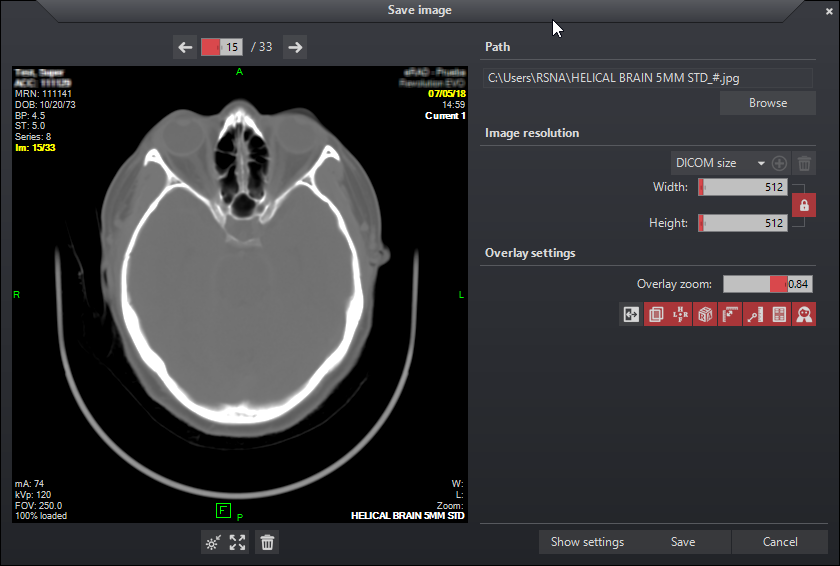

Az eRAD PACS nézegető lehetővé teszi a felhasználónak a képadatok mentését a helyi munkaállomásra korlátozott standard formátumok használatával.

A Kép mentése panel olyan gyűjtőterület, amely képek gyűjtésére szolgál fájlba mentésük előtt. A Kép mentése panel a fő nézegető munkaterülethez hasonlóan eszközöket biztosít a képjellemzők beállításához. Az ablakszint, a nagyítás és a képpásztázás módosításai az előnézeti panelen belüli képekre alkalmazhatók az alapvető egérfunkciók használatával.

A felhasználó kézzel vagy a Tallózás gomb kiválasztásával határozhatja meg a fájlok elérési útját. A megjelenítő öt képformátumot támogat: JPG, PNG, GIF, TIFF és BMP. A formátumot a fájlböngésző ablak lenyíló listájából lehet kiválasztani, vagy megfelelő kiterjesztéssel lehet megadni a fájlnév végén az elérési út szövegmezőben. Ha a fájlnév nem végződik érvényes kiterjesztéssel, a rendszer a felhasználót a „Mentés” gombra kattintáskor figyelmezteti, akinek lehetősége van a kívánt formátum megadására vagy az alapértelmezett (JPEG) formátum elfogadására.

A képfelbontás a csúszkák segítségével adható meg. A maximális felbontás oldalanként 10 000 pixel. Az aktuális képarány alapértelmezés szerint zárolva van, és a ![]() zárolás gombra kattintva oldható fel. Ha az arány zárolva van, a csúszkák együtt mozognak a képarány fenntartása érdekében.

Rendelkezésre áll egy előre meghatározott felbontásokat tartalmazó lenyíló lista. A DICOM méret visszaállítja a képet az eredeti méretre. A felhasználó új bejegyzéseket adhat hozzá és menthet a csúszkák beállításával, majd a ![]() Hozzáadás gombra kattintva. Válasszon ki egy mentett értéket, majd nyomja meg a

Az overlay információ mérete az Overlay nagyítás csúszka segítségével módosítható.

Különböző eszközök állnak rendelkezésre a képtulajdonságok és -információk vezérlésére:

Az előnézeti panel felett navigációs eszközök állnak rendelkezésre. A nyilak vagy a csúszka segítségével mozoghat a betöltött képek között. Emellett az egérgörgő görgetésével a betöltött képek között is navigálhat.

Az előnézeti panel alatt eszközök találhatók a képjellemzők visszaállításához és eltávolításához.

A képbeállítások exportálása a Beállítások megjelenítése gombra kattintva érhető el